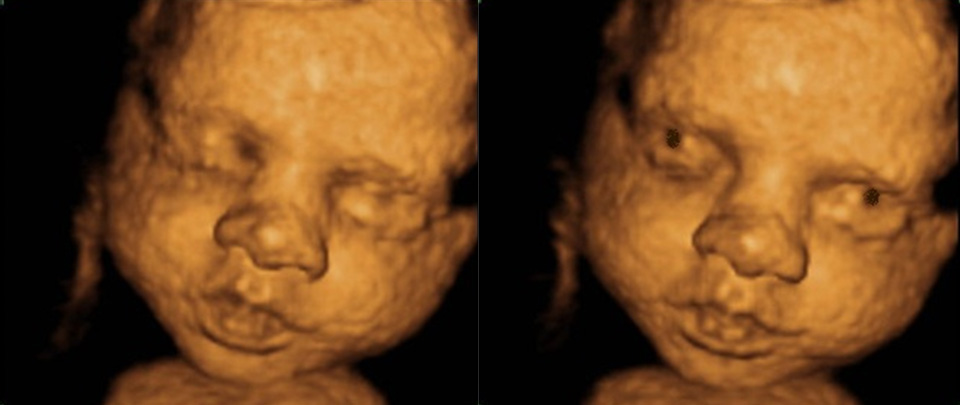

Υπερηχογράφημα Β’ Επιπέδου ή αναλυτικό υπερηχογράφημα (20-24 εβδομάδες): πραγματοποιείται στο δεύτερο τρίμηνο της εγκυμοσύνης και μελετά λεπτομερώς την ανατομία του εμβρύου με στόχο να προσδιοριστεί η πορεία της εγκυμοσύνης.

Υπερηχογράφημα ανάπτυξης-Doppler (24-40 εβδομάδες): πραγματοποιείται στο τρίτο τρίμηνο της εγκυμοσύνης και μας δίνει μια ολοκληρωμένη εικόνα σχετικά με την ανάπτυξη και τη θρέψη του εμβρύου σε συνδυασμό βέβαια και με τις υπερηχογραφικές εξετάσεις που έχουν προηγηθεί.